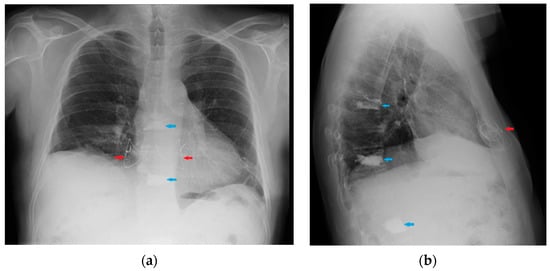

7. Chest Tubes

| Chest tubes | Kinking Extrapleural/intrafissural/intraparenchymal/misposition Mediastinum juxtaposition Diaphragmatic trespassing Mediastinal invasion (uncommon) |